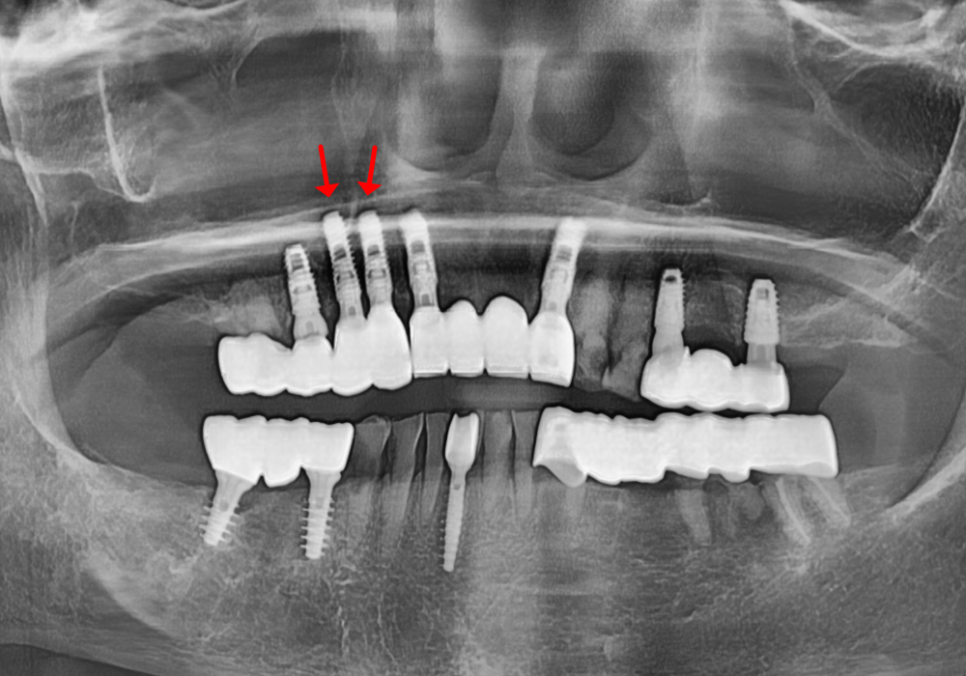

해놓은 임플란트는 잘 쓰고 계셨는데,

이번에는 임플란트 옆 치아인,

오른쪽 위 치아(#13, #14)가

부러져 내원하셨습니다.

250503

확인해 보니 이번에도

충치 범위가 넓고

뿌리가 짧아진 상태라

보존적으로 살리기

어렵다고 판단했습니다.

250510

그래서 동일하게

발치 후 임플란트로 진행했고,

이 역시 약 3개월 뒤 보철을 완성했습니다.

250728